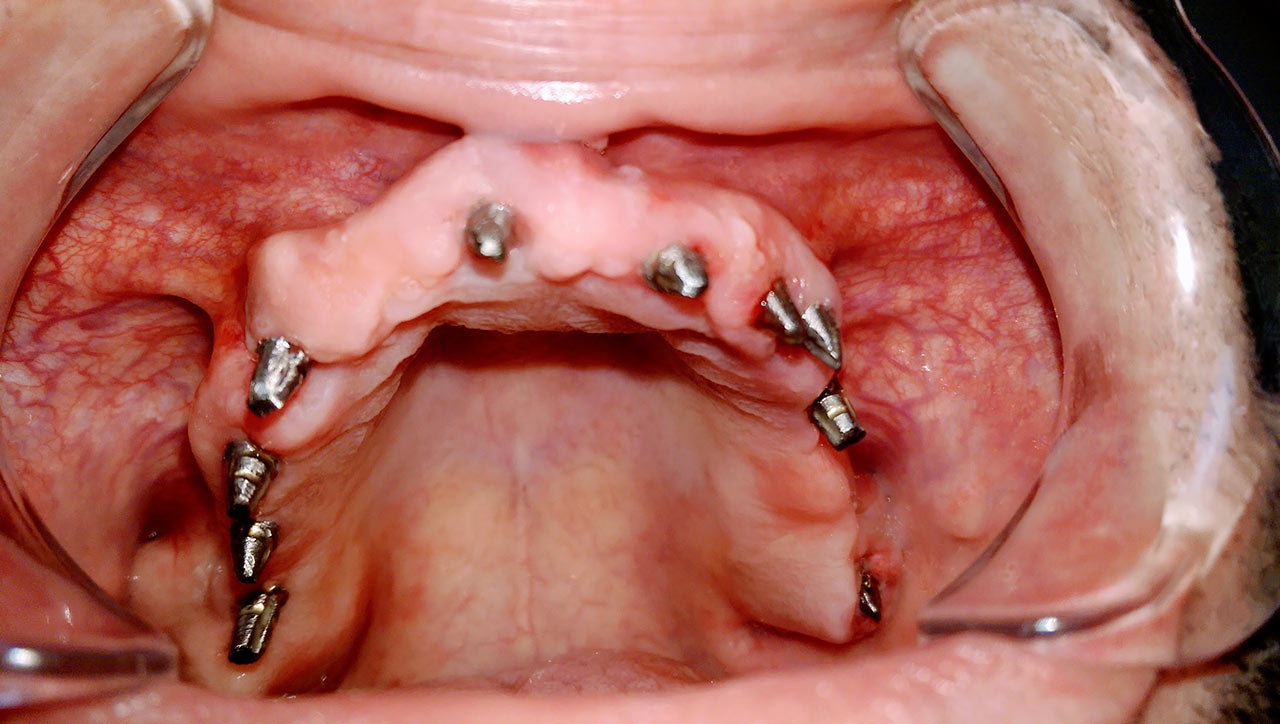

Teljes fogatlanság helyreállítása 2 nap alatt

Teljes fogatlanság helyreállítása 2 nap alatt azonnal terhelhető svájci IHDE implantátumokkal és PMMA műanyag hidakkal. Intraorális szkennerrel vettünk lenyomatot az implantáció után, és erre a digitális mintára készítette el a fogtechnika a hidak digitális tervezését, majd faragta ki műanyagból. Ezt a gyors munkát az azonnal terhelhető implantátumok és a digitális lenyomat, tervezés segítségével tudtuk megcsinálni mindössze 2 nap alatt. Dr. Kelemen Péter és a Symbion Fogtechnika munkája.